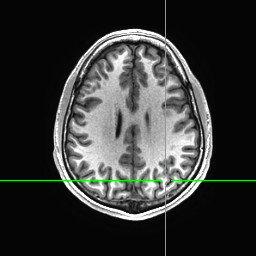

We trained MAP, MC Bernoulli Dropout (BD), and Spike-and-Slab Dropout (SSD) Meshnet-like CNNs on the 9,298 sMRI volumes in the training set. We then applied our networks to produce segmentations for both the in-site test set and the out-of-site test data. For the BD and SSD networks, 10 MC samples were used for test predictions. The means and standard deviations across volumes for the average Dice across all 50 classes are shown in Table 3. Dice scores for each label for the in-site and out-of-site test sets are shown in Figure 2 and 3, respectively. We found that, compared to MAP and BD, SSD significantly increased the Dice for both the in-site () and out-of-site () test sets, per a paired t-test across test volumes. We found that SSD had a 5.7% drop in performance from the in-site test set to the out-of-site test set, where as the MAP has a drop of 6.2% and BD a drop of 5.4%. This is better than drops of 9.4% and 7.8% on average reported in the literature by Roy et al. (2018b) and Roy et al. (2018a), respectively. In Figures 4 and 5, we show selected example segmentations for the SSD network for volumes that have Dice scores similar to the average Dice score across the respective dataset.